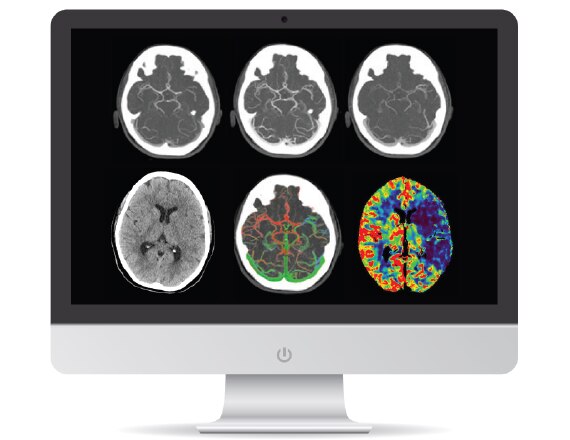

A patient with suspected TIA or stroke will typically receive a general and neurological examination followed by diagnostic brain imaging, performed immediately on arrival so that treatment can be started promptly.3 Optimal scanning coupled with workflow applications and protocols designed for stroke help deliver accurate and quick diagnosis to impact patient outcomes.

Revolution brand of CT systems

Capable of acquiring neuro perfusion and CTA of the brain in a single exam to enable comprehensive functional and anatomical assessment.

FastStroke CT Application

Simplifies and organizes CT images for fast evaluation of Stroke patients.

Fast Brain protocol with HyperWorks

Providing structural as well as vascular information with improved resolution and precise characterization in 5 minutes.